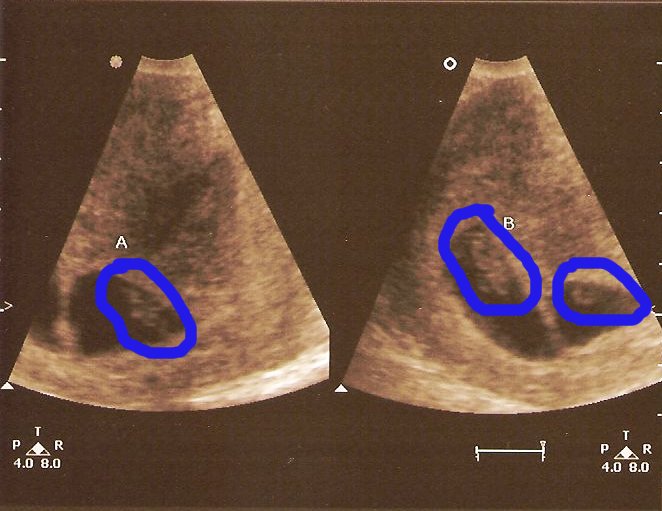

Regina had an appointment with the baby doctor at 8:00 AM yesterday. The nurse operating the ultrasound machine told us she would first look at the top of her stomach before looking at the babies closeup (at 8 weeks, they would be the size of kidney beans). Then she told us something we were not expecting, or prepared for. Regina is carrying TWINS!!!! Both of our jaws had to be picked up off the floor. My eyes were watering, and my head was spinning. The nurse then went in for a closer view to do the measurements, heart rate, etc. These pics are from the closeup view. Even at this small size we could easily see their heart beat. The twins are due November 29, 2007.